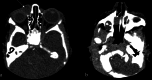

The lacrimal gland is a bilobed serous gland located in the superolateral aspect of the orbit. Lacrimal system pathologies can be broadly divided into pathologies of the lacrimal gland and those of the nasolacrimal drainage apparatus. These include distinct congenital, infectious, inflammatory, and benign, indeterminate, and malignant neoplastic lesions. Trauma and resultant fractures affecting lacrimal drainage apparatus is not part of this review; only non-traumatic diseases will be discussed. CT is the initial modality of choice because of its ability to delineate lacrimal system anatomy and demonstrate most lacrimal drainage system abnormalities and their extent. It also assesses bony architecture and characterizes any osseous changes. MRI is helpful in further characterizing these lesions and better assessing involvement of the surrounding soft tissue structures. In this pictorial review, we will review the anatomy of the lacrimal system, describe CT/MRI findings of the common and uncommon lacrimal system abnormalities and discuss relevance of imaging with regards to patient management.